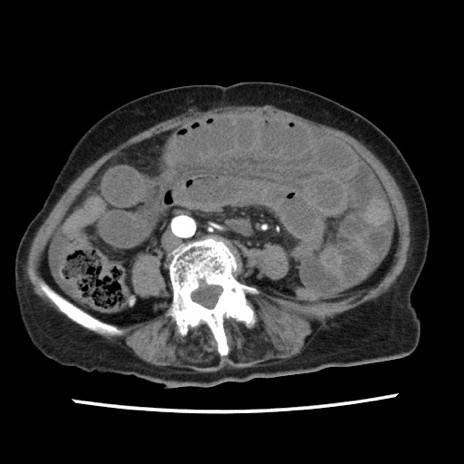

症例1(横断像)

【症例】80歳代女性

【主訴】腹痛

【現病歴】8時間前から腹痛あり来院。

【既往歴】糖尿病、脂質異常症、子宮体癌にて子宮全摘術

【身体所見】意識清明・会話良好だが腹痛で苦悶様、全腹部にわたって反跳痛と圧痛あり

【データ】WBC 13600、CRP 0.14、LDH 224、CK 90